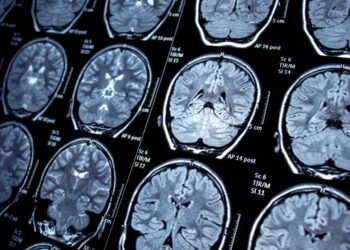

Emerging Research on Mold: Neurological Consequences Uncovered

Mold is a type of fungus that grows in damp and humid environments, both indoors and outdoors. Exposure to mold ...

Mold is a common household problem that can cause a variety of health issues. While most people associate mold with ...